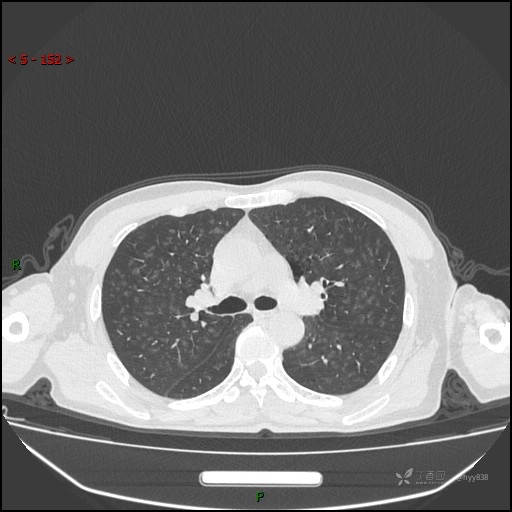

呼吸科电话会诊病例:过敏性肺炎 VS 吸烟相关间质性肺炎 VS 尘肺……结果公布~

性别:男

年龄:55岁

简要病史:渐进性呼吸困难。

胸部CT平扫

电焊工尘肺 (2)